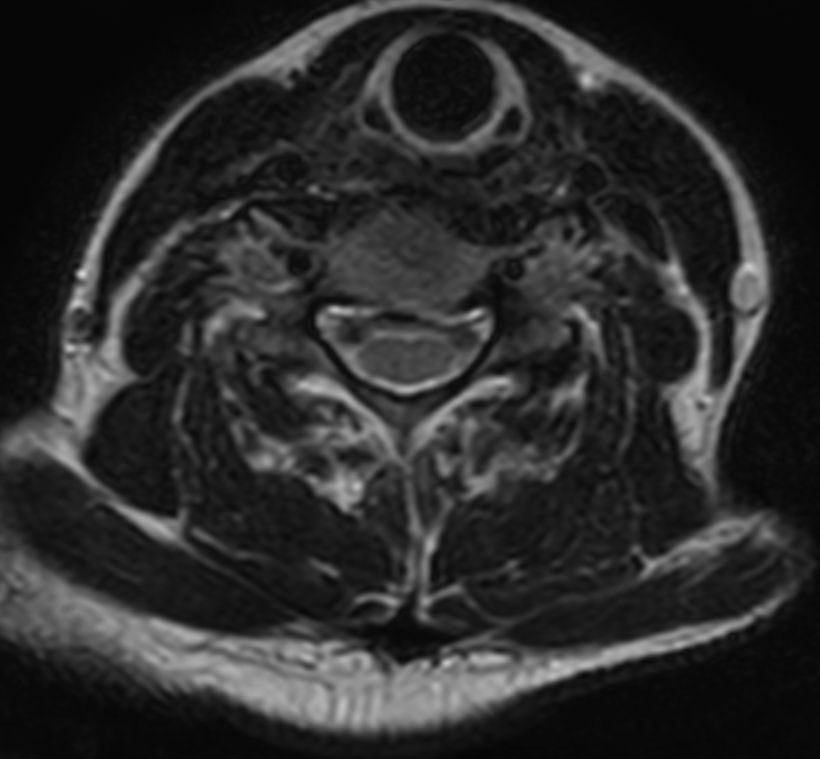

mFFE